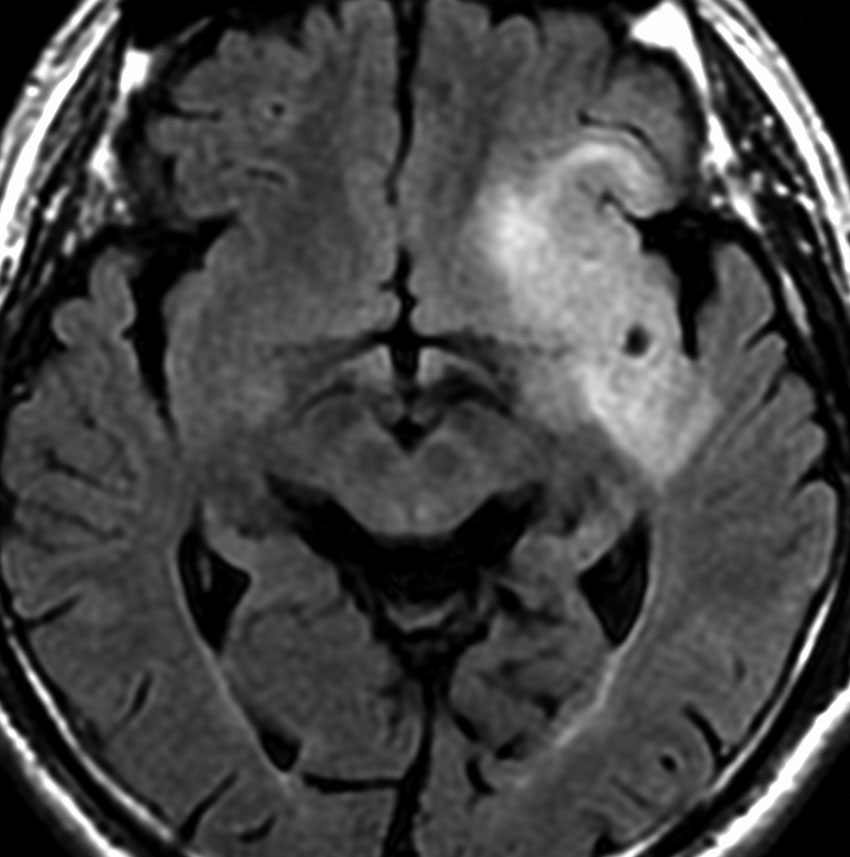

若い女性の左前頭葉から島回,側頭葉を侵す腫瘍で,てんかん発作で発症し,開頭生検 biopsy しました。

一部で,細胞密度が高く,核の腫大とクロマチンの増量,核間距離の短縮があり,核分裂像が認められ,MIB-1染色率が10%です。組織学的には退形成性乏突起膠腫グレード3とされました。

IDH変異あり,1P/19q欠失あり,ATRX変異なしです。

乏突起膠細胞系グリオーマなので,放射線治療の高線量領域はあまり広くとりません。

IMRT Simultaneous Integrated Boost (SIB)で,FLAIR高信号の領域に54グレイ27分割,周囲仮定浸潤領域 generous local areaに46グレイを照射しました。

テモゾロマイド75mg/m2を併用しています。

左の画像は放射線治療直後のMRIですが,すでに腫瘍の縮小がみられます。

テモゾロマイドの維持療法は,24コース 2年間行い,それ以降は無治療としました。

照射後7年の画像です。腫瘍は縮小したまま,患者さんは無症状で経過しています。